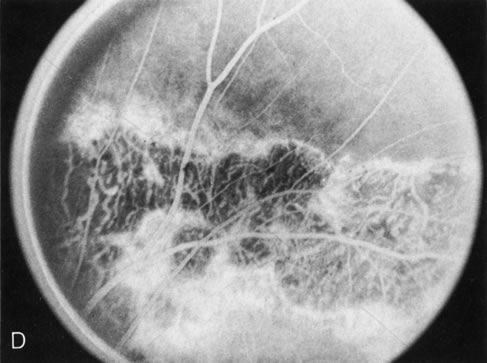

Fig. 1. Retinitis pigmentosa. A. A typical area of bone spicule pigmentation. B. Diffuse dye leakage is apparent throughout the posterior pole. C. The early angiogram shows dilated and irregular retinal radial peripapillary capillaries and perifoveal retinal capillaries. D. Leakage from these vessels are evident in the late angiogram.

Of more clinical importance is the role of FA in the diagnosis and treatment of cystoid macular edema (CME) (Fig. 1C and D). Stereoscopic FA indicates that the leakage, which may be diffuse or have the typical petaloid stellate appearance of CME, can come from the perifoveal retinal capillaries, from the choroid through the RPE, or from a combination of both sources.4 With the recent suggestion that CME in RP may be successfully treated with acetazolamide,5, 6 FA is thus important to document the diagnosis of CME, establish the origin(s) of leakage, and follow patients during and after therapy.